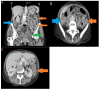

Herein, we present a case of cytomegalovirus (CMV) colitis that occurred after two cycles of azacitidine and venetoclax in a 64-year-old woman affected with acute myeloid leukaemia (AML) secondary to a previous diagnosis of a hypoplastic myelodysplastic syndrome (hypo-MDS). This patient never had detectable CMV viraemia, and there was no evidence of immune deficiency that could justify this opportunistic infection. Additionally, this is most likely the first report describing CMV colitis in a patient treated upfront with azacitidine and venetoclax.